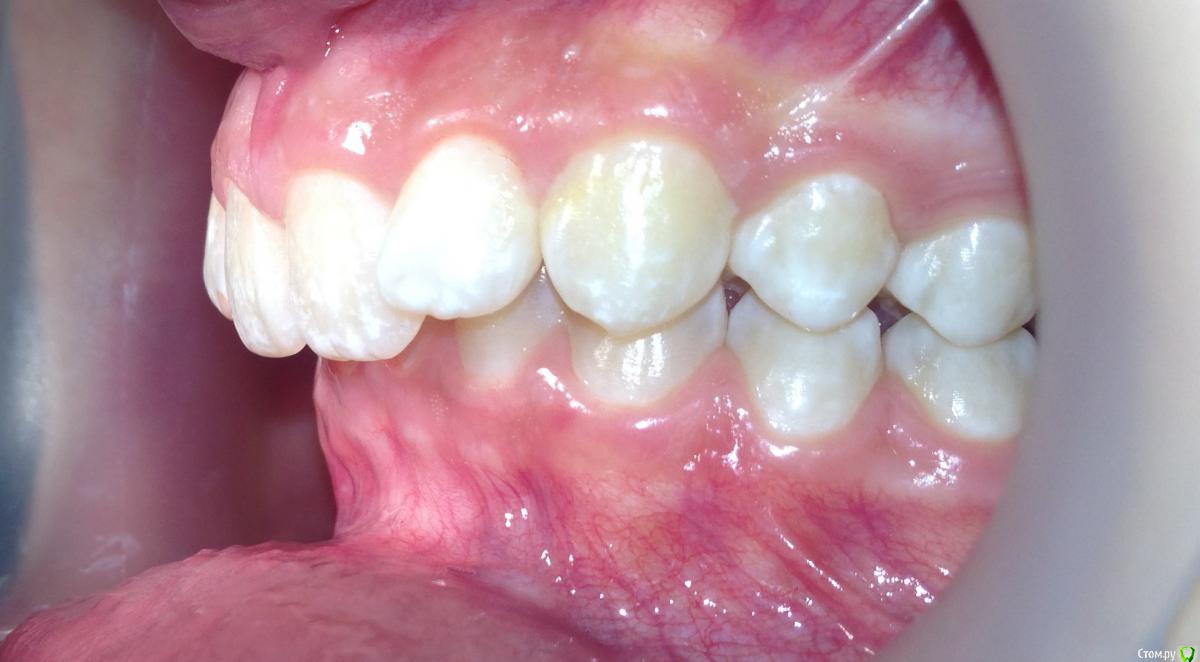

post-38874-0-87186300-1459536185_thumb.jpgpost-38874-0-15339500-1459536188_thumb.jpgpost-38874-0-82577500-1459536190_thumb.jpgpost-38874-0-61079300-1459536193_thumb.jpgpost-38874-0-22178300-1459536196_thumb.jpgpost-38874-0-56404400-1459536198_thumb.jpgpost-38874-0-43380300-1459536199_thumb.jpgpost-38874-0-04081600-1459536228_thumb.jpgpost-38874-0-34503200-1459536230_thumb.jpgpost-38874-0-34236500-1459536233_thumb.jpgpost-38874-0-95387400-1459536234_thumb.jpgpost-38874-0-86290600-1459536242_thumb.jpgpost-38874-0-47956700-1459536252_thumb.jpgpost-38874-0-98507600-1459536273_thumb.jpgpost-38874-0-52220700-1459536283_thumb.jpgpost-38874-0-12327700-1459536263_thumb.jpg

Извините за качество фото.

Пациентка 14 лет. Было принято решение лечить без удаления, тк. профиль не позволяет да и ретропозиция нч. Лечение идет. Я назначила ранние эластики слабые, на 17/25 нити на вч и 18 нити на нч. по 2 классу короткие 3,4-4,5. Пациентка пришла через месяц жалуется на щелканье челюсти во время ношения эластиков и сразу после их снятия. Т.е. если открывает рот, то челюсть скачкообразно двигается и щелчками. Последние 2 недели, когда много говорит, то вообще стала заедать. Это она так сказала. После отмены эластиков (страшно), через неделю пришла, рот открывает ровно, без девиации, щелчков нет. Вопрос: почему щелкает и что с этим делать? По поводу прикуса, посоветуйте, пожалуйста, как нормализовать? Аппарат типа гербста? может ей твинблок сделать? Эластики? К сожалению другими методами я пока что не владею. Спасибо, очень жду ваших советов.

Мне кажется, Вы сами ответили на свой вопрос. Поставьте несъемный аппарат (типа твин форс или форсус...). Они легки в креплении и использовании. Даже при таких аппаратах бывает рецедив, не то что от эластиков (поэтому их не использую при дистальном).

Конечно, через интеонет трудно ответить, ведь щелчки бывают разные (в начале фазы открывания, в конце, в начале фазы закрывания, в конце закрывания? То есть если у нее смещена головка кзади ппи щакрытом рте, то при открывании у нее сразу должен быть щелчок (головка догнала диск), пожевала .., потом во время закрытия в самом конце опять щелчок (головка съехала с диска и стала в свое привычное положение). Это обычная картина при втором классе. Несьемные аппараты не будут давать уходить челюсти назад, щелчков быть не должно. После снятия аппарата зафиксируете новое положение челюсти бугорками антагонистов